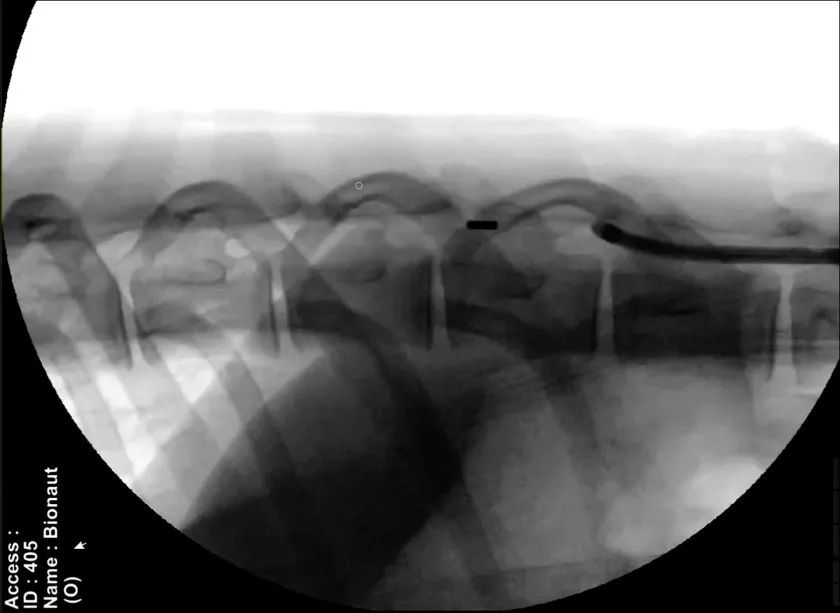

是行得通的。具体而言,该公司会在其首次临床试验中把装载着治疗药物的微型机器人注射到脊柱中,并使用一组位于头部和颈部周围的磁铁产生的磁场将机器人引导进入脑部患病区域。在到达正确的位置后,另一个磁信号将激活机器人药物舱的开关,释放药物。药物卸载后,医生再引导机器人返回至起始点,将其从脊柱处接离。

图|Bionaut微型机器人进入活羊的蛛网膜下腔(来源:BionautLabs官网)

Shpigelmacher进一步解释道,目前的技术已经允许机器人制造得足够小,但为了确保其能够在X光下实时清晰可见、方便追踪和操控,Bionaut将微型机器人的大小尽可能保持在1毫米左右。